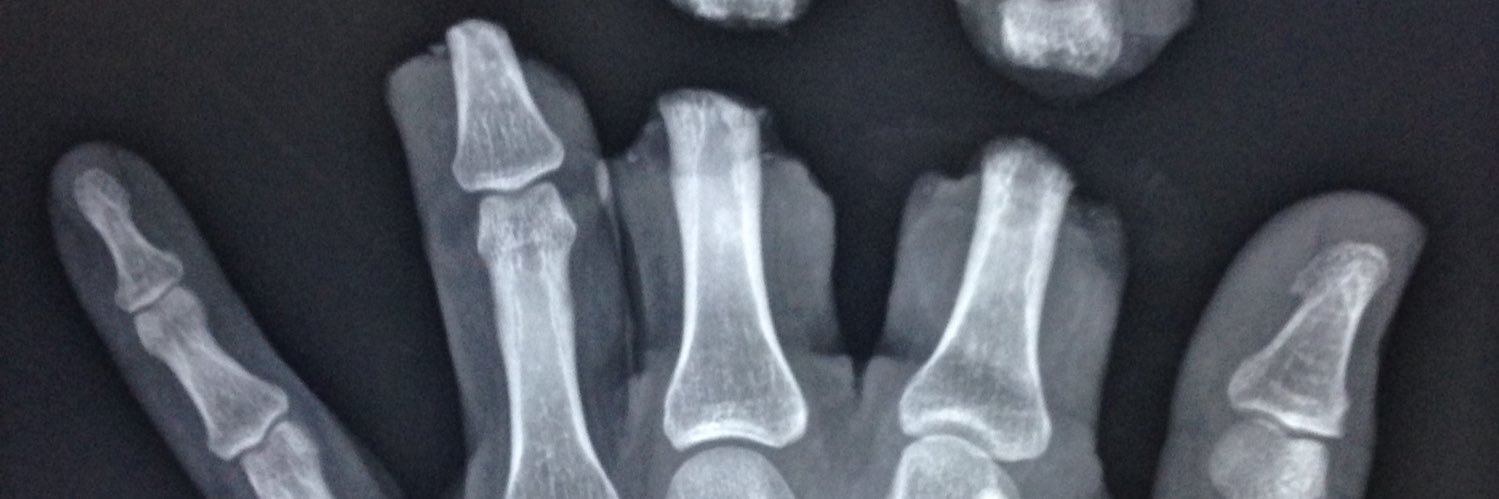

@xraydolly

Senior lecturer in Radiography- UoD, Reporting rad, Prof Doc student, brain haemorrhage survivor, NICE guidelines PIP expert Yorkshire lass- all views my own.